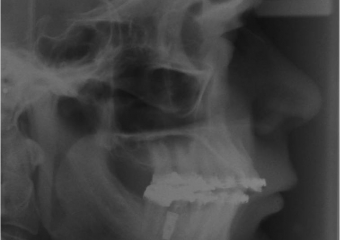

Telerradiografia após a cirurgia